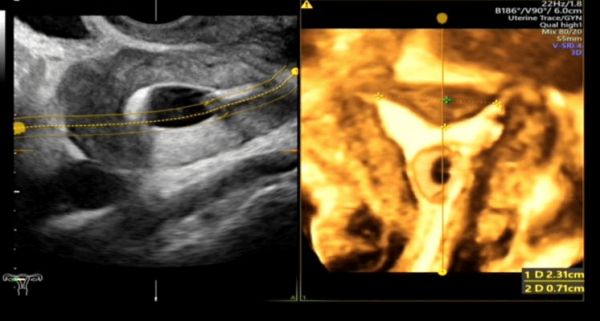

简单来说,这是一项评估输卵管通畅性的医学影像检查技术。检查时,医生会在宫腔内放置一根双腔造影管,通过推注造影剂,动态观察造影剂在宫腔、输卵管和盆腔的流动、积聚和弥散情况,从而判断输卵管的通畅度、走形以及病灶部位。通过这个快速安全的检查,输卵管的许多问题便能一目了然。

超声造影能实时、动态、多角度、多方位观察输卵管走行形态,对输卵管通畅程度的判断较客观、准确。在推注造影剂的过程中,液体产生的压力对输卵管内部轻微的粘连或堵塞能起到一定的疏通作用。

单角子宫合并右侧残角

子宫内膜息肉